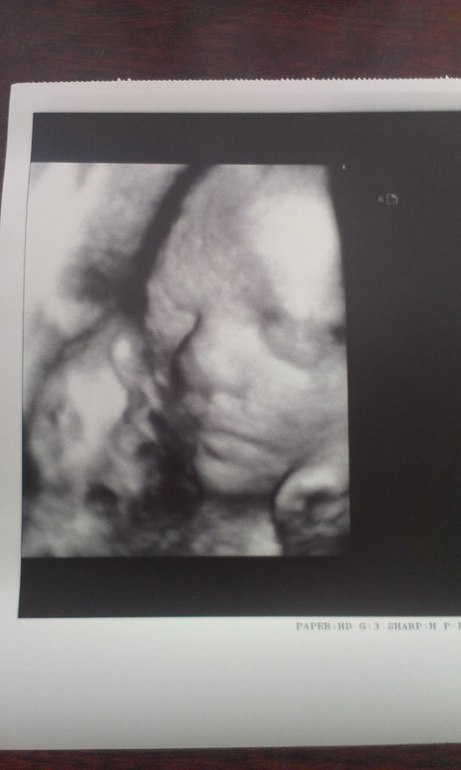

Узи и доплер показали хорошие результаты. Развиваемся отлично, плацента выполняет все свои функции как надо, лежим головкой вниз. Вес малыша 1550 гр. Определили и ПДР по узи 13 ноября, он полностью совпадает с моими подсчётами))))

Фото нашего малыша на 28-й недельке